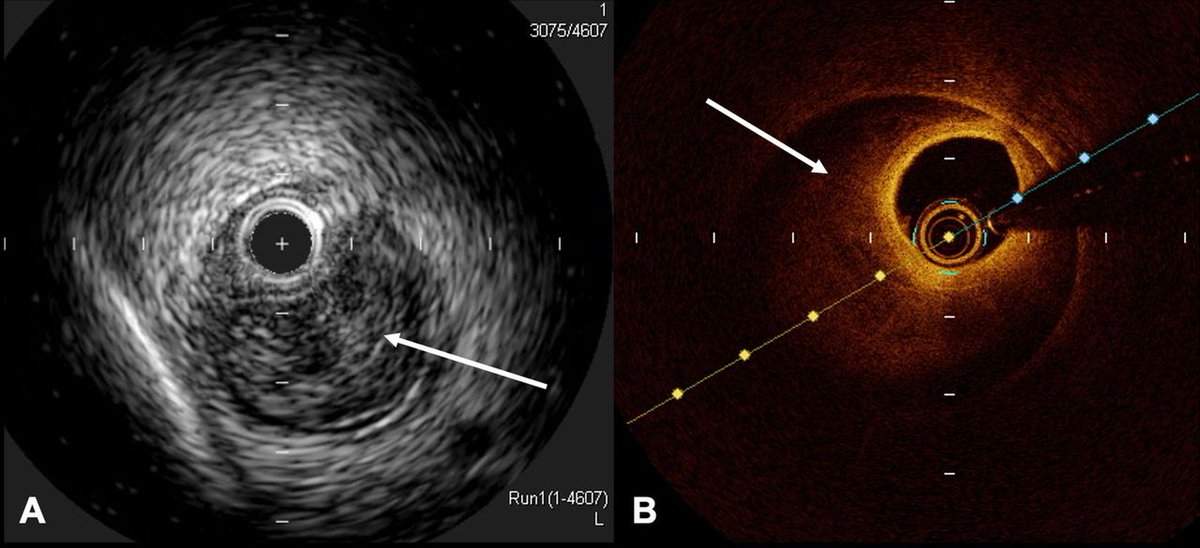

#CoronaryMicrovascularDysfunction drives ischemia & prognosis in #cardiomyopathy. How can #CMD assessment improve risk stratification & therapy?

Discover the latest insights from @fedegcb, @p_meynet, @R_A_Cimino, @morena_arianna et al. in this review.